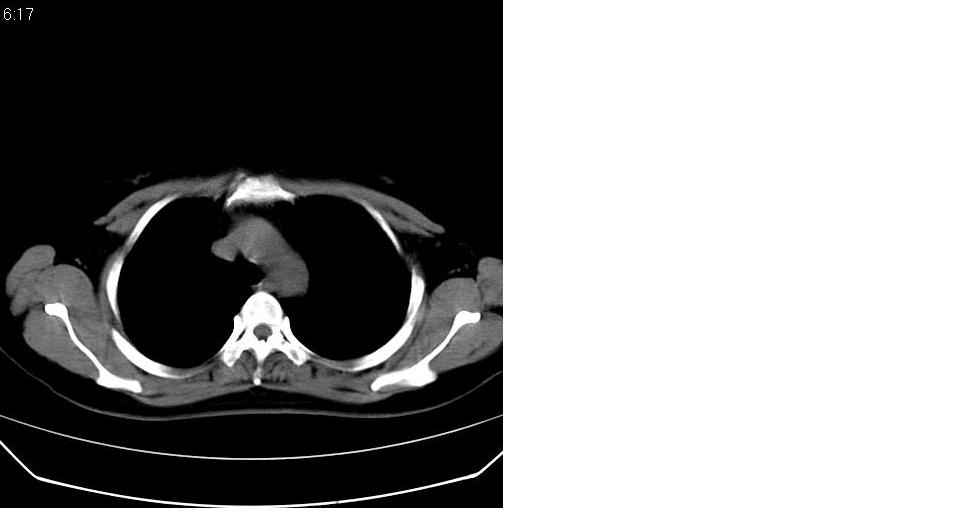

女 40岁,胸片体检发现右肺肿块,无任何症状。

下叶背段多发性小腺泡结节,考虑结核。

考虑右肺下叶背段继发性肺结核。